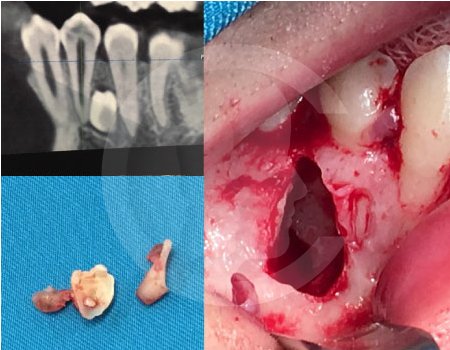

Antes de la extracción se realiza una valoración clínica y estudios de imagen, como radiografías panorámicas o tomografías, para conocer la posición del tercer molar, su relación con los nervios y planificar un procedimiento seguro y adecuado para cada paciente.

No es recomendable. Antes de extraer terceros molares es necesario realizar una valoración clínica y estudios de imagen para conocer la posición del diente, su relación con los nervios y el tipo de procedimiento más seguro para cada paciente.

Algunas extracciones simples de otras piezas dentales pueden ser realizadas por un odontólogo general; sin embargo, por la complejidad que presentan los terceros molares, o si se encuentran retenidos, impactados o cerca de estructuras importantes, se recomienda que el procedimiento sea realizado por un cirujano maxilofacial para mayor seguridad y control del tratamiento.